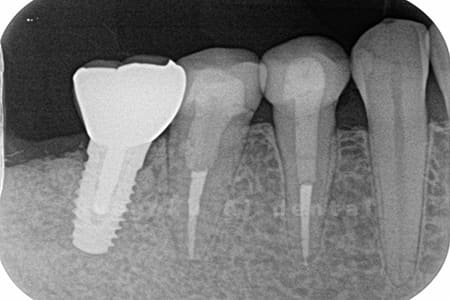

- 縁下カリエス、慢性根尖性歯周炎、不良補綴

- クラウンレングスニング、マイクロエンド、フルジルコニアクラウン

虫歯が神経まで及ぶと共に、歯茎の中まで虫歯が及んでいました。根の治療(マイクロエンド・根管治療)を行なった後、クラウンレングスニング・歯周外科を行い、ジルコニアの被せ物を行った患者様です。